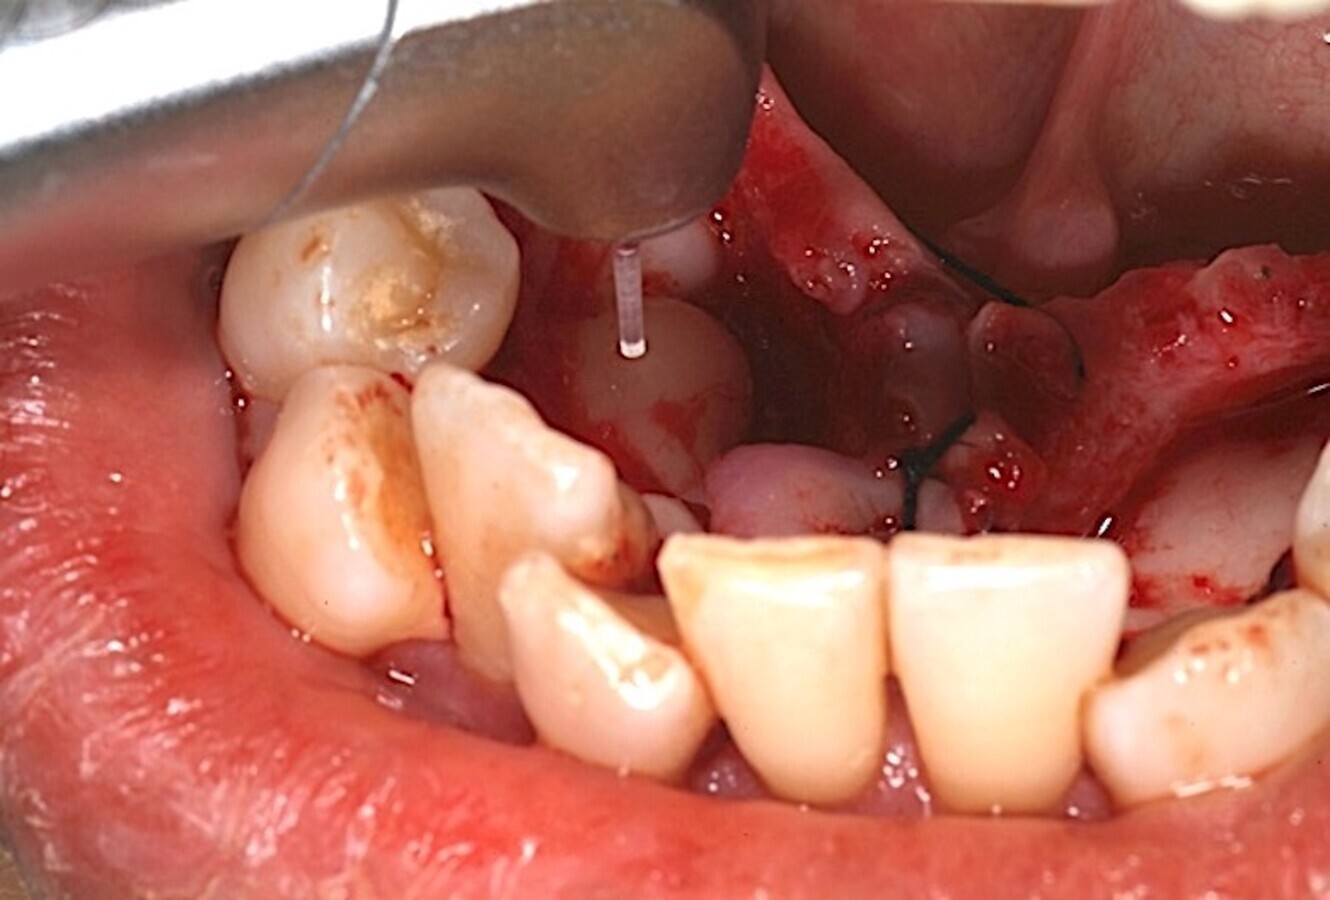

Algunos láseres como los de erbio, y en mi día a día en concreto el de Er,Cr:YSGG (Waterlase), permiten realizar un corte óseo quirúrgico muy preciso (Figuras 9-13), que transmite un daño térmico mínimo a los tejidos adyacentes9.

El láser Er,Cr:YSGG de alta potencia permite realizar cortes óseos quirúrgicos muy precisos (ver Figuras 9-13).

Figura 9.

Figura 10.

Figura 11.

Figura 12.

Figura 13. Las figuras 9-13 permiten observar un corte óseo quirúrgico muy preciso realizado con láser de erbio que produce un daño térmico mínimo en los tejidos adyacentes.